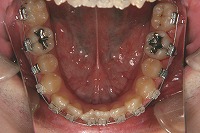

下顎

反対咬合と下顎が出ている事を主訴に来院された、初診時18歳1か月の男性です。診断「上顎骨の後方位による骨格性反対咬合」非抜歯での矯正治療と、下顎を後退させる外科手術を併用して治療を行いました。